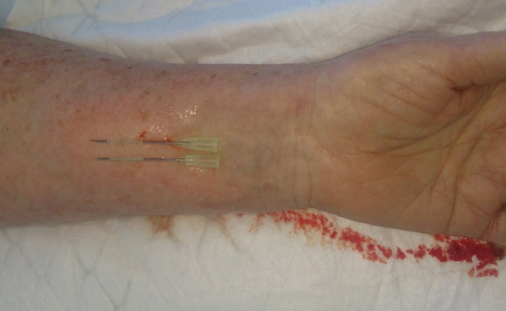

Далее делаем новокаиновую «подушку» в месте взятия лоскута и внутрикожно проводим параллельно 2 инъекционные иглы так, чтобы они просвечивались. Выходим с противоположной стороны «подушки». Должно получиться, как на рисунке.

Затем скальпелем, начиная от кончиков игл, скользим по получившимся рельсам к пластиковой части, как показано на фото.

На иглах переносим лоскут на дефект и аккуратно подшиваем. Стараюсь использовать мононити 6/0 или 5/0.